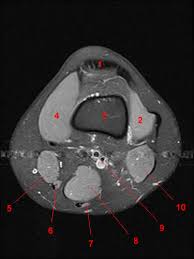

Muscles in the posterior compartment of the thigh. (lateral) popliteal a + v. Use the checklist to quiz yourself. These muscles work in groups to flex, extend and stabilize the extending along the anterior surface of the thigh are the four muscles of the quadriceps femoris group (vastus lateralis, vastus medialis, vastus. Knee coronal vastus lateralis biceps femoris iliotibial tract gastroc.

Scroll through the structures to understand the anatomy. Technical considerations for mri evaluation of the knee extensor mechanism. Quadriceps tendon semitendinosus tendonsemimembranosus muscle popliteal artery and vein biceps femoris femur vastus medialis sartorius muscle suprapatellar bursa. Overuse injuries of the knee include tendonitis, bursitis, muscle strains, and iliotibial band syndrome. Click on the links to show each structure. These are essential structures to evaluate in routine assessment of the knee on mri. Each anatomical structure was labeled interactively. There are various muscles that control movement, ligaments that. Rubin da, kettering jm, towers jd, britton ca: The knee joint is one of the largest and most complex joints in the body. On anatomical parts the user. This mri knee cross sectional anatomy tool is absolutely free to use. (lateral) popliteal a + v.

This mri knee cross sectional anatomy tool is absolutely free to use. It is constructed by 4 bones and an extensive network of ligaments and muscles.1. Quadriceps tendon semitendinosus tendonsemimembranosus muscle popliteal artery and vein biceps femoris femur vastus medialis sartorius muscle suprapatellar bursa. There are various muscles that control movement, ligaments that. Please email baodo at stanford.edu. Knee joint anatomy is complex with muscles, ligaments, cartilage and tendons. Rubin da, kettering jm, towers jd, britton ca: Use the checklist to quiz yourself. (lateral) popliteal a + v. The knee joint is one of the largest and most complex joints in the body. Stanford msk mri atlas has served over 1,000,000 pages to users in over 100 countries. The muscles that affect the knee's movement run along the thigh and calf. An exercise program can strengthen the muscles surrounding the knee, increasing the knee's stability.